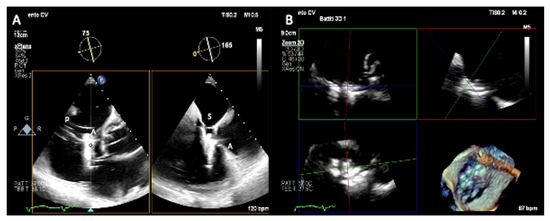

2.1. Two-Dimensional and Three-Dimensional Transthoracic and Transesophageal Echocardiography

3.1. Two-Dimensional and Three-Dimensional Transesophageal Echocardiography